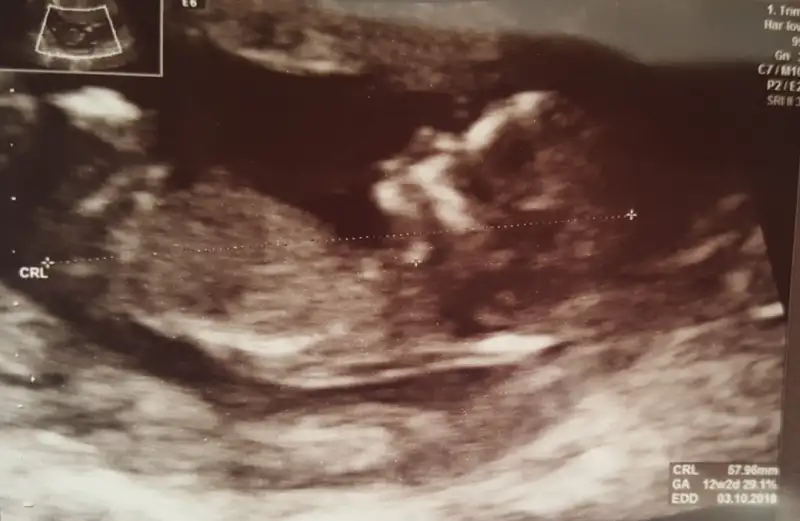

Çok şükür maşallah canım gözün aydın hep güzel haberler alalım inşallahMerhaba kizlar, bugun kontrolum ve ikili testim vardi. Guzelde gecti, cok sukur hersey yolunda suan icin. Test sonuclari 1 hafta sonra cikacakmis, dr tlf ile konusuruz dedi.

Merhaba kızlar nasılsınız? Bugün 2li testi yaptırdık. Ben de çok kararsızdım yaptırıp yaptırmamak konusunda ama doktorumla konuştuktan sonra yaptırmaya karar verdim. Doktor cinsiyet konusunda birşey demedi. Bu haftalarda cinsiyet tomurcuğu oluşuyor ve ne söylesem yanıltıcı olur dedi. 18. Hafta öğrenmek için en ideali dedi. Testin sonucunu da çarşamba günü alacağız. Çok şükür bir sıkıntımız yok. Inşallah test yaptıran herkesin sonucu iyi çıkar.

Önce ultrason sonra kan şeklinde yapıldı.Ikili testde sadece kanmi verdiniz ultrason sonrami çekiliyor